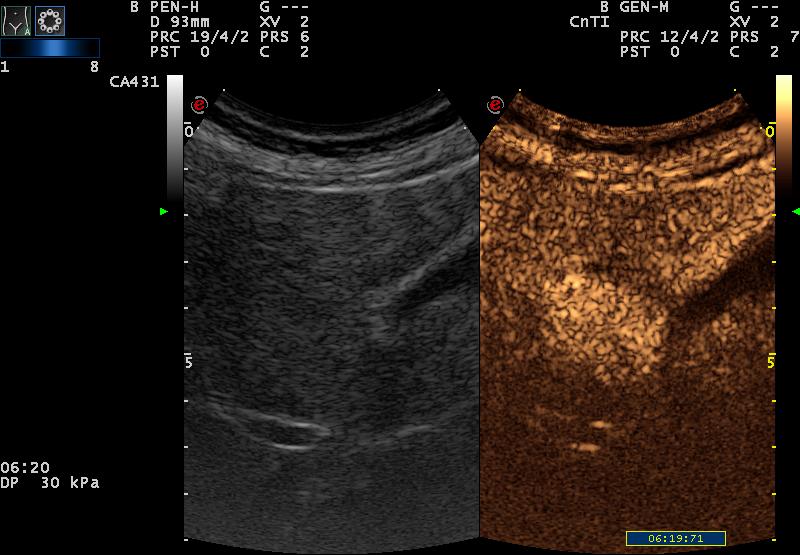

| késői fázisban (6. perc) még mindig jobban halmoz a környezeténél |

Ez utóbbi cikk szerint (ellentétben a szakirodalomban általában leírtakkal) kontrasztanyagos UH vizsgálattal késői fázisban az adenoma a környező parenchymánál jobban halmoz.